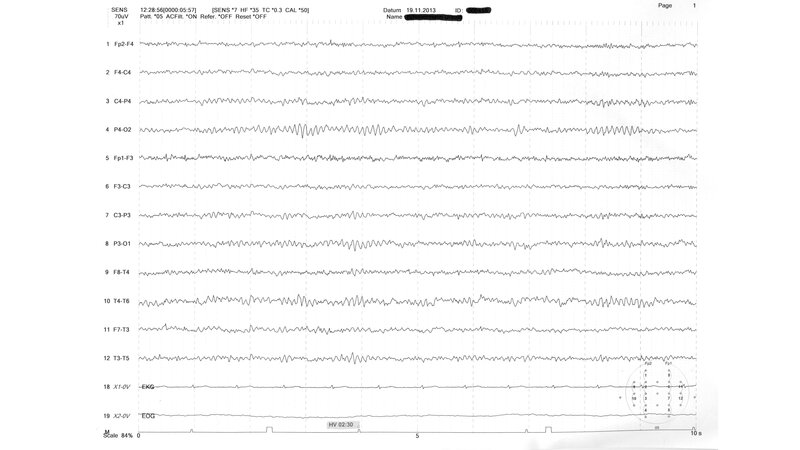

Das EEG ist ein wichtiges Diagnoseinstrument der Neurologie. Registriert wird dabei die bioelektrische Aktivität bestimmter Gehirnregionen auf der Kopfhaut. Es gibt typische EEG-Muster, welche sich speziellen Krankheitsbildern zuordnen lassen, zum Beispiel Sharp-Waves im Sinne von epilepsietypischen Potenzialen.